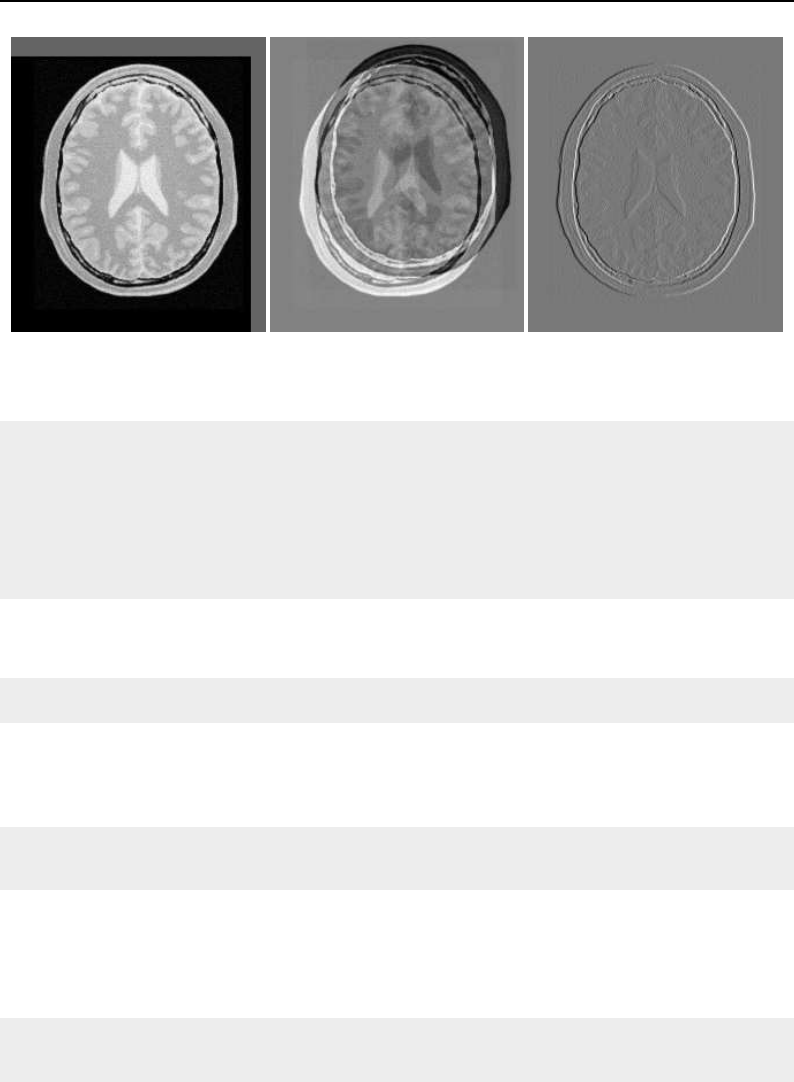

The National Library of Medicine Insight Segmentation and Registration Toolkit, shortened as the

Insight Toolkit (ITK), is an open-source software toolkit for performing registration and segmenta-

tion. Segmentation is the process of identifying and classifying data found in a digitally sampled

representation. Typically the sampled representation is an image acquired from such medical instru-

mentation as CT or MRI scanners. Registration is the task of aligning or developing correspondences

between data. For example, in the medical environment, a CT scan may be aligned with a MRI scan

in order to combine the information contained in both.